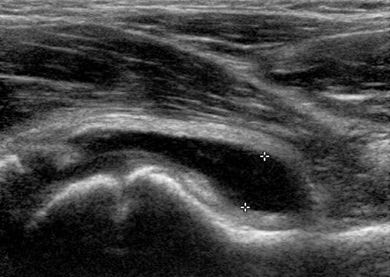

Imaging is not strictly necessary, but an ultrasound is often requested to confirm the presence of a joint effusion. Radiography is only performed when there are other differential diagnostic considerations. The appearance of the effusion on ultrasound is not helpful for the differential diagnosis.

Figure 3. Anechogenic effusion in the hip (between markers).